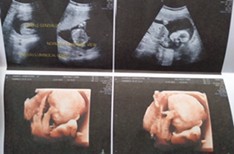

ซาวด์ตอน17 w ค่ะชัดมากก

3เดือนเหมือนกันจ้า😁